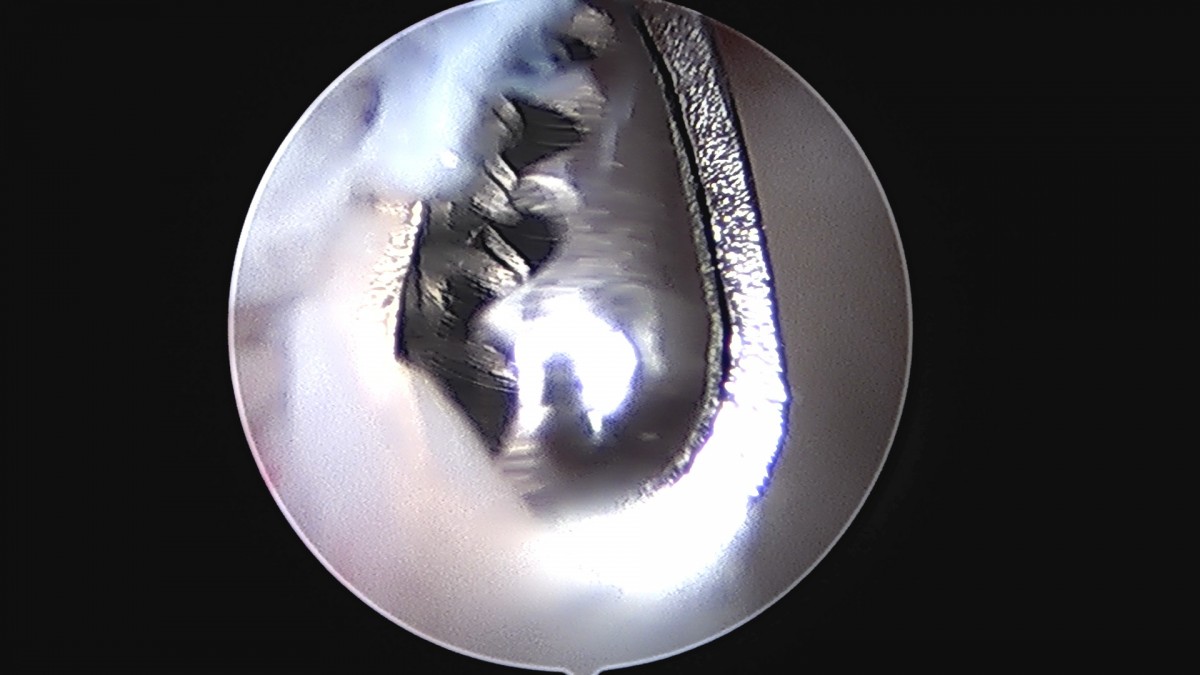

정지영원장님 손목 삼각섬유연골 복합체 봉합술 박현O 환자

dae765e4d9ac96aee867c9d6292d8784_1758009005_5023.jpg